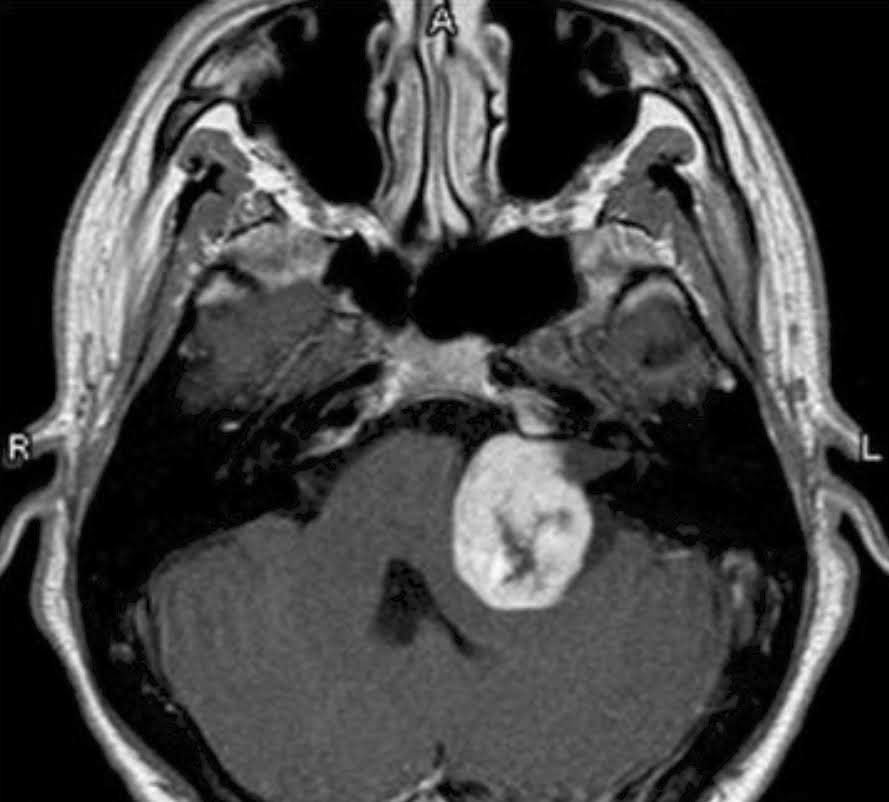

The Beyond Recovery Project brings together brain tumour survivors, creating a ‘safe’ space and sense of community where they can move forward, beyond recovery.